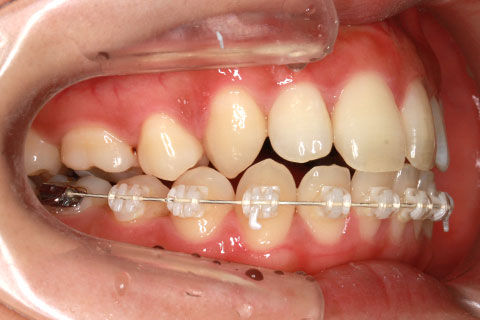

ハーフリンガル矯正3(上の歯のみ舌側矯正で治療)

治療前

治療中(開始直後)

治療中(開始半年後)

治療後

- 年齢・性別

- 25歳女性

- 治療期間

- 2年0ヶ月

- 抜歯

- 上下4番抜歯

- 治療費

- 110万円

- 備考

- 治療内容

- 施術の副作用(リスク)

- 表側矯正と比較して、力学的な操作性が複雑なため、ボーイングエフェクトを起こしやすい。